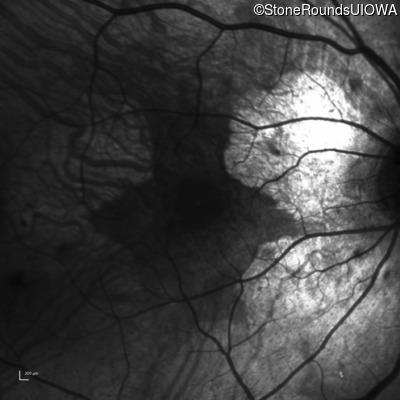

Infrared Fundus Photograph - Right - 20/16

Exemplar